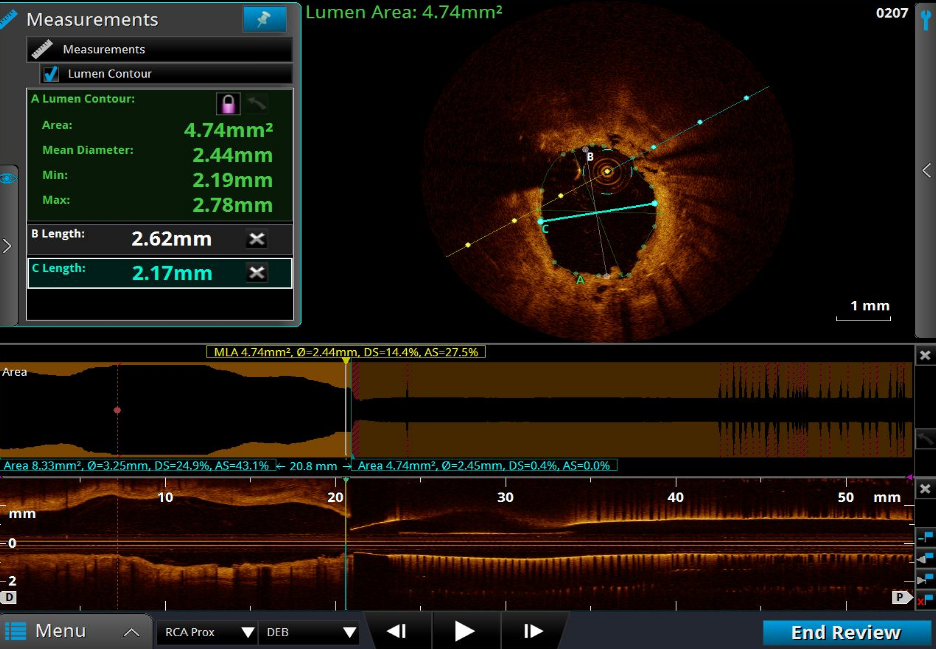

LCX—OCT术前检查

回旋支近段,远段ISR,最狭窄平均直径1.26mm;管腔面积 1.26mm²;以纤维斑块为主。

LCX—OCT术后检查